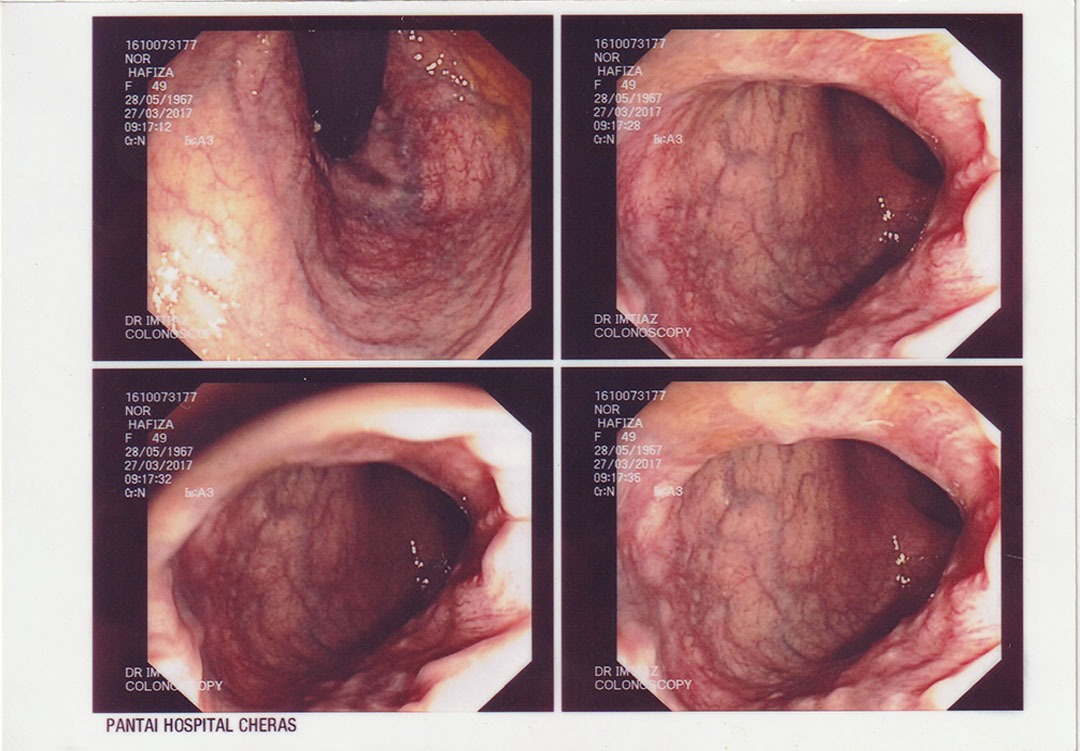

Pada tahun 2016, saya mula mengalami ketidakselesaan yang teruk pada bahagian perut, pergerakan usus yang tidak teratur, dan gejala membimbangkan yang mengganggu kehidupan seharian. Apabila menerima diagnosis serius mengenai kesihatan sistem pencernaan saya, dunia terasa gelap seketika. Saya bimbangkan masa depan suami dan anak-anak. Alhamdulillah, suami saya terjumpa risalah Ibnu Sina Wellness™ di surau dan mencadangkan agar saya mencubanya sebagai jalan sokongan ke arah pemulihan.

Saya memulakan perjalanan bersama Ibnu Sina Wellness™ pada Januari 2017 dengan penuh harapan. Hasilnya sungguh luar biasa! Dalam tempoh beberapa bulan, pemeriksaan menunjukkan sistem dalaman saya beransur-ansur pulih dengan sendirinya. Menjelang 2018, pemerhatian klinikal menunjukkan saluran pencernaan saya telah kembali ke tahap yang sangat sihat dan cergas. Pendekatan ini bukan sahaja menyokong pemulihan fizikal, malah menguatkan kesejahteraan emosi dan spiritual saya.